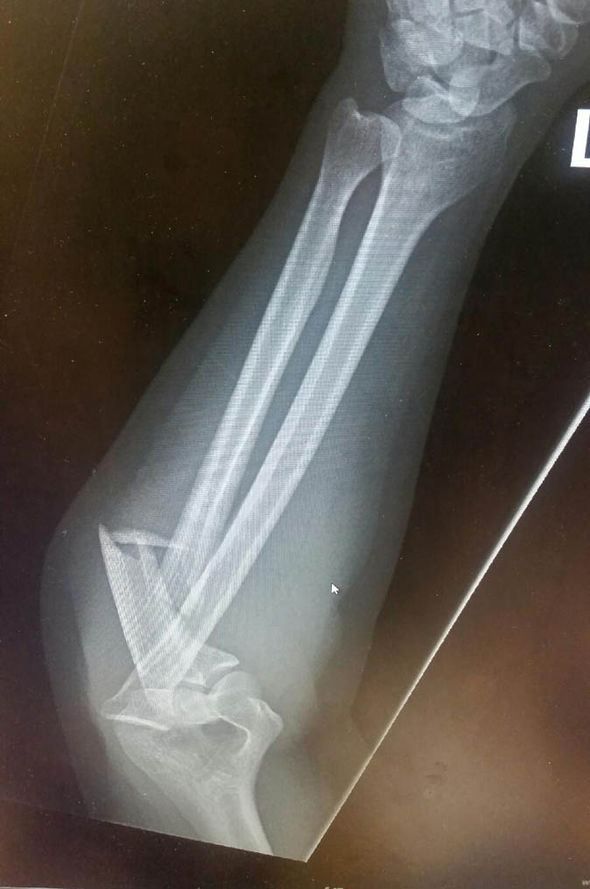

La foto è stata pubblicata sul social networking Reddit con il titolo “L’ignoranza da ubriachi è beatitudine” dall’utente QuercusPercus che sosteneva di essere coinquilino della paziente. Reddit ha pubblicato anche una radiografia del braccio rotto della ragazza.

“Credo che il conto sarà più terrificante di questa immagine”, ha detto un amico della ragazza che ha riportato due fratture all’avambraccio – ulna e radio – e un gomito slogato. Infatti dal momento che la ragazza non ha una assicurazione medica, probabilmente ha smesso di ridere ben presto. Il conto, infatti, è stimato tra i 4mila e i 50mila euro.